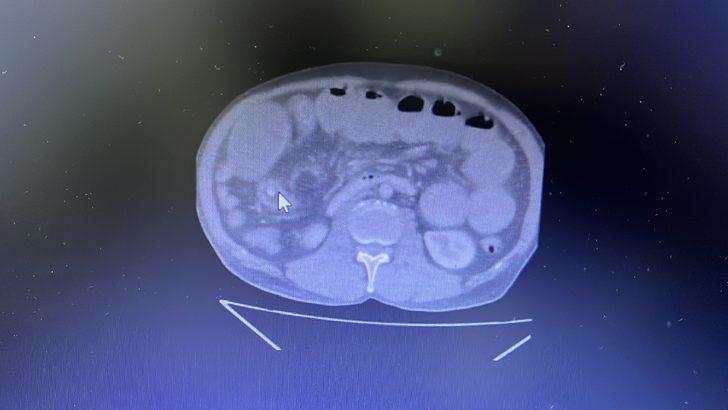

Uzun süredir mide yanması şikayeti bulunan Gül, arkadaşının "Hastalığına iyi gelir." tavsiyesiyle 4 zeytin yuttu. Mide yanması karın ağrısı, bulantı ve kusmaya dönüşünce özel bir hastaneye kaldırılan Gül'ün ince bağırsağında tümöre benzer bir cisim tespit edildi. Acil ameliyata alınan Gül'ün ince bağırsağında tümör zannedilen kitlenin zeytin olduğu anlaşıldı.

Ameliyat anında yaşadığı şaşkınlığı anlatan Genel Cerrahi Uzmanı Dr. Muhammed Yılmaz, başarılı operasyonla zeytinin çıkarıldığını ve hastanın ağrılarından kurtulduğunu söyledi.

İlk etapta kitlenin zeytin olabileceğinin akıllarına gelmediğini belirten Yılmaz, "Açıkçası ben safra taşı olabilir diye düşünmüştüm, ameliyat işlem sırasında tıkanıklık olan yeri açtığımızda içinden zeytin tanesi çıktığını gördük." dedi.

Yılmaz, operasyon sırasında şaşkınlık yaşadıklarını ifade ederek ameliyat sonrasında hastanın 4 zeytin yuttuğunu öğrendiklerini anlattı.

Vatandaşlara meyve ve sebzelerin çekirdeklerini yememeleri tavsiyesinde bulduklarını vurgulayan Yılmaz, "Mide rahatsızlığı bulunanların doktora gidip muayene olduktan sonra endoskopi yapılıp ona göre ilaç kullanmalarını tavsiye ediyoruz. Hastamız ameliyattan önce 2 haftadır büyük abdestini yapamıyordu. Şu an hastamızın gayet iyi durumda." diye konuştu.